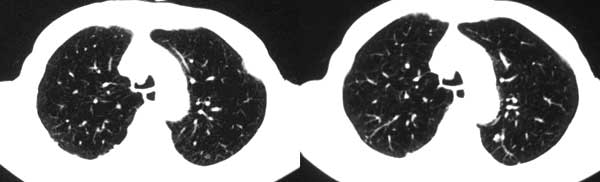

本例病人肺内多发结节灶、双侧肋骨破坏、胸椎椎体及椎弓破坏应是肾癌转移。请大家分析气管内结节灶性质?另外还得麻烦领导给删掉那多余的那幅图。谢谢了!

双肺多发结节状影,腹膜后见肿大淋巴结,支持肾ca转移

双肺内多发结节影是转移灶没问题,气管内的还应该商榷

肺内 肋骨 椎体转移已确定,气管内阴影不象结节,气管内壁无增生,显示层面只有一层,纵隔窗见不到,多考虑粘痰核.